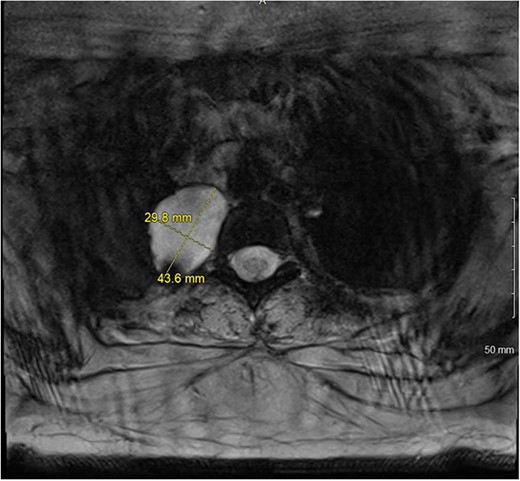

A 36-year-old female presented to an outside emergency department reporting chest pain, dizziness and abdominal pain for 7 hours. A computed tomography (CT) angiogram of the chest revealed a right paraspinal 4.2 × 2.8 × 3.3-cm cystic mass at the level of T2-3, which was well-circumscribed (Figs 1 and 2).

CT chest with IV contrast transverse view with detailed measurements of right T2-T3 paravertebral mass.